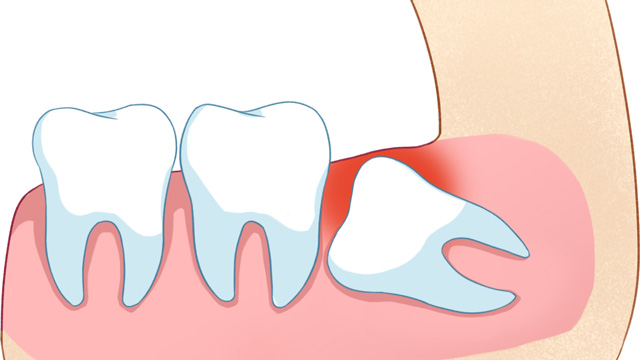

03智齿位置不正,未来存在潜在风险

有些智齿虽然目前没有疼痛、没有挤压邻牙,但拍X光片后发现,它属于“埋伏阻生”(完全埋在牙龈下),或者生长方向异常,未来很可能会萌出、挤压邻牙,甚至引发囊肿、肿瘤等问题。对于这类堪比“定时炸弹”的智齿,医生通常会建议拔除,避免后续出现更严重的口腔问题。

智齿萌出时,牙龈会形成一个“盲袋”,容易堆积食物残渣和细菌,进而引发“智齿冠周炎”——牙龈红肿、疼痛、流脓,严重时还会导致脸颊肿胀、发烧,影响正常饮食和生活。